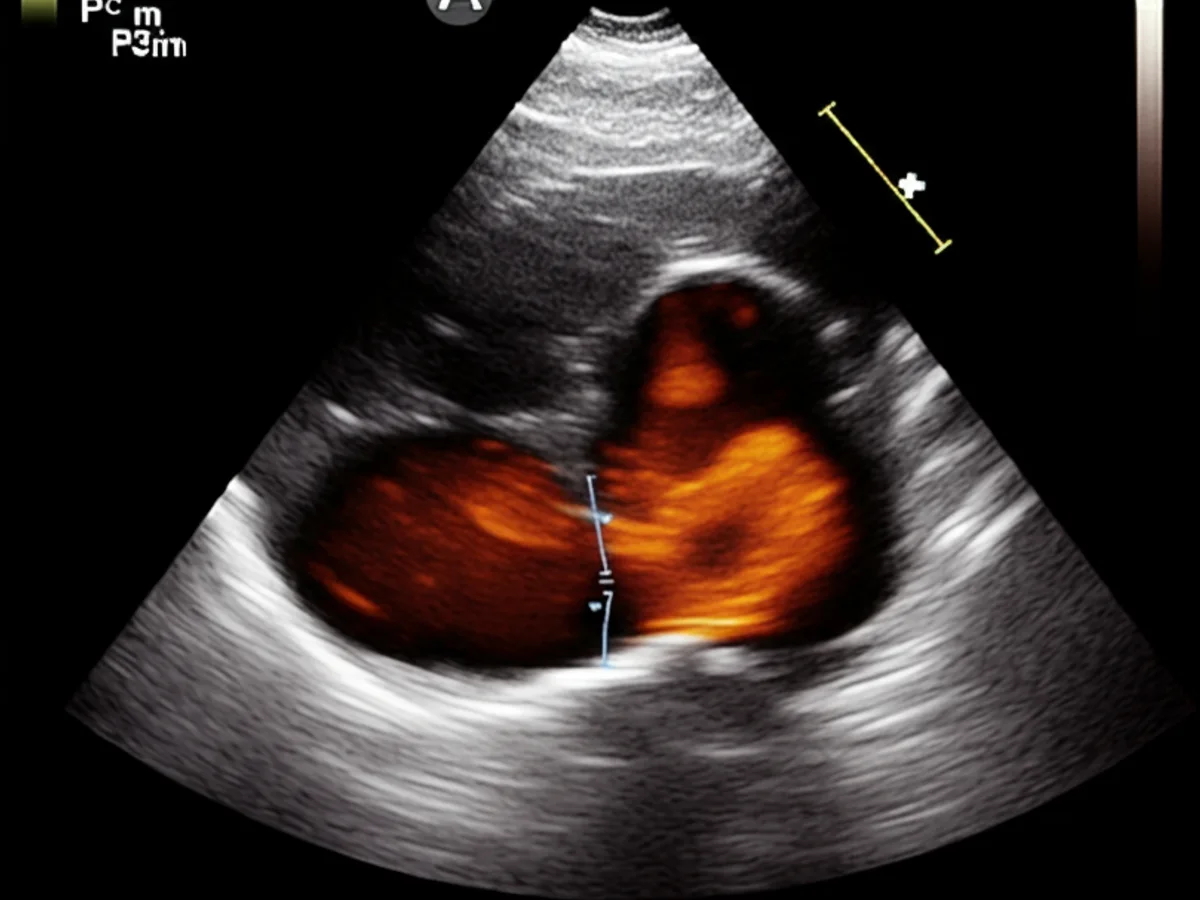

Die Diagnose von felinem Asthma erfolgt meist durch eine Kombination aus klinischer Untersuchung und speziellen Tests: